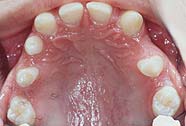

Bei Birgitte Fosner sind 11 Zähne, sowohl im Oberkiefer als auch im Unterkiefer nicht angelegt. (*Aplasie)

Im Oberkiefer sind es 5 Zähne, die ihr fehlen, (4,2 + 2,4,7).

Eine Zahnregulierung wird innerhalb eines Jahres mit Hilfe einer festen Spange durchgeführt, um Platz für 2 Implantate zwischen den Vorderzähnen und den Eckzähnen zu schaffen und die Backenzähne dahinter zu richten.

Nach der Zahnregulierung werden 2 Implantate als Ersatz für die fehlenden Vorderzähne (2+2) eingesetzt. Die Backenzähne werden mit einer Brücke rekonstruiert.